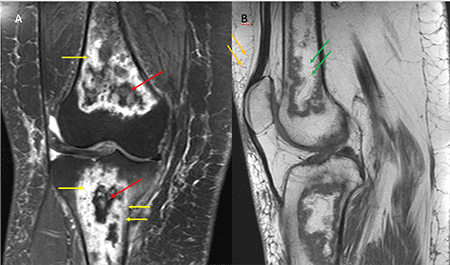

Ressonância magnética (RM) do joelho direito evidenciando lesões com aspecto geográfico acometendo grande parte das porções visualizadas da tíbia e do fêmur, caracterizando infartos ósseos. Em A, sequência DP com supressão de gordura (SG) no plano coronal mostra lesão com baixo sinal em sua porção central (seta vermelha), associada a edema adjacente (seta amarela). Em B, sequência T1 no plano sagital evidenciando lesão com margens serpiginosas e alto sinal no interior (setas verdes), provavelmente por conteúdo gorduroso (notar que o interior da lesão tem o mesmo sinal da gordura do tecido subcutâneo – seta laranja).

RM de joelho, sequência ponderada em DP com SG no plano sagital, observa-se o sinal do duplo contorno, caracterizado por um halo de hipersinal na margem interna da lesão representando tecido de granulação (seta amarela), e um halo de baixo sinal na margem externa, representando osso esclerótico (seta vermelha).